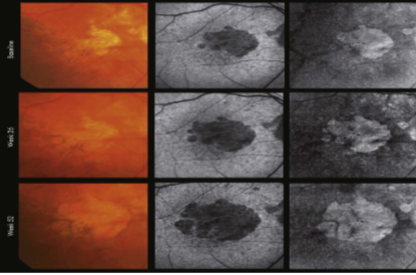

disciform scarring

final stage of MNV in which there is progressive fibrosis & loss of the macular photoreceptors function

seen less often now w/ anti-VEGF therapy

exudative macular degeneration

fibrosis